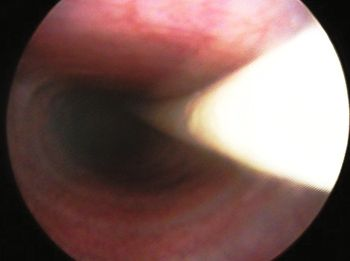

La bronchoscopie peut être utilisée pour confirmer un collapsus de la trachée et des voies aériennes et pour évaluer la gravité de la maladie (Figure 4). C’est probablement la meilleure méthode disponible pour diagnostiquer une bronchomalacie impliquant plusieurs segments lobaires (Figure 5). Elle peut également confirmer la nature dynamique de la maladie dans les voies aériennes plus petites. La bronchoscopie peut également aider à repérer une bronchectasie (Figure 6) ou d’autres changements irréversibles tels que des nodules de bronchite ou des proliférations inflammatoires dans les voies respiratoires (Figure 7). Cette technique permet enfin de faire des prélèvements dans les voies respiratoires pour explorer une maladie infectieuse ou inflammatoire des voies respiratoires (Figure 8). Chez un chien présentant un collapsus des voies aériennes, la bronchoscopie peut cependant s’avérer risquée, en particulier chez un individu obèse ou anxieux présentant une grande sensibilité trachéale ou des efforts expiratoires marqués. L’anesthésie peut altérer les réflexes respiratoires qui maintiennent les voies respiratoires ouvertes et le chien aura alors du mal à récupérer correctement de l’anesthésie. En outre, l’excitation au réveil peut entraîner des efforts abdominaux excessifs qui aggravent le collapsus des voies respiratoires basses.